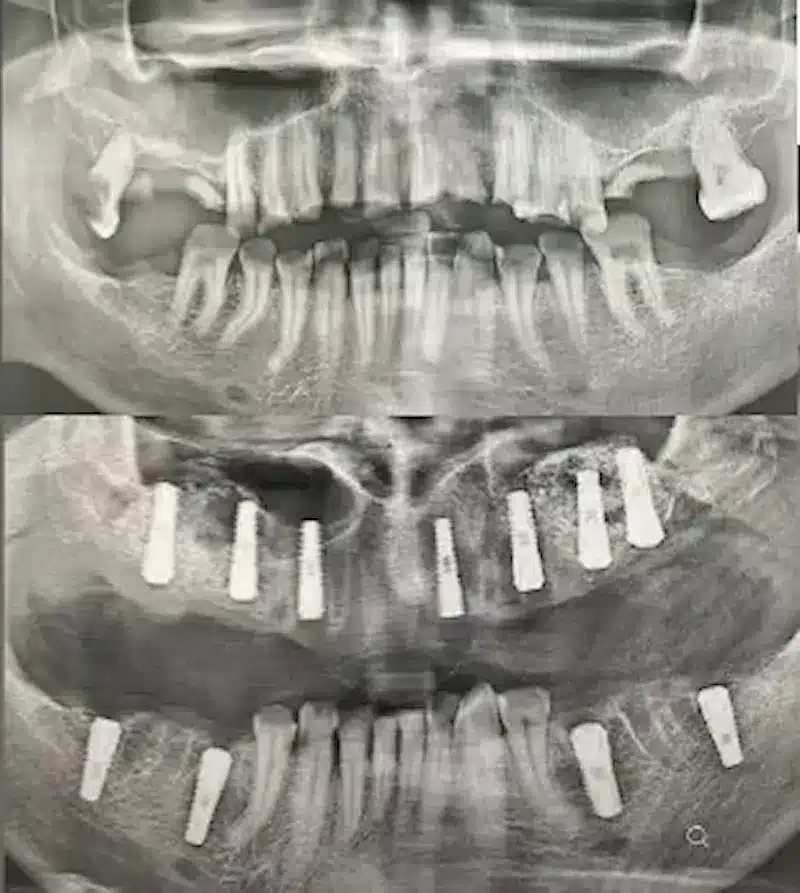

Dr. Seden Aksu is a specialist in modern implantology and surgical dentistry with extensive experience in the management of complex clinical cases. In her practice, she applies comprehensive surgical planning, minimally invasive techniques, and advanced regenerative technologies aimed at restoring both the function of the dentoalveolar system and the aesthetics of the smile. Dr. Aksu has significant experience in performing implant procedures, bone augmentation, and periodontal surgery, including the treatment of patients with severe bone loss. The primary goal of her work is to achieve stable, long-term outcomes in implant rehabilitation and the restoration of oral tissue health.